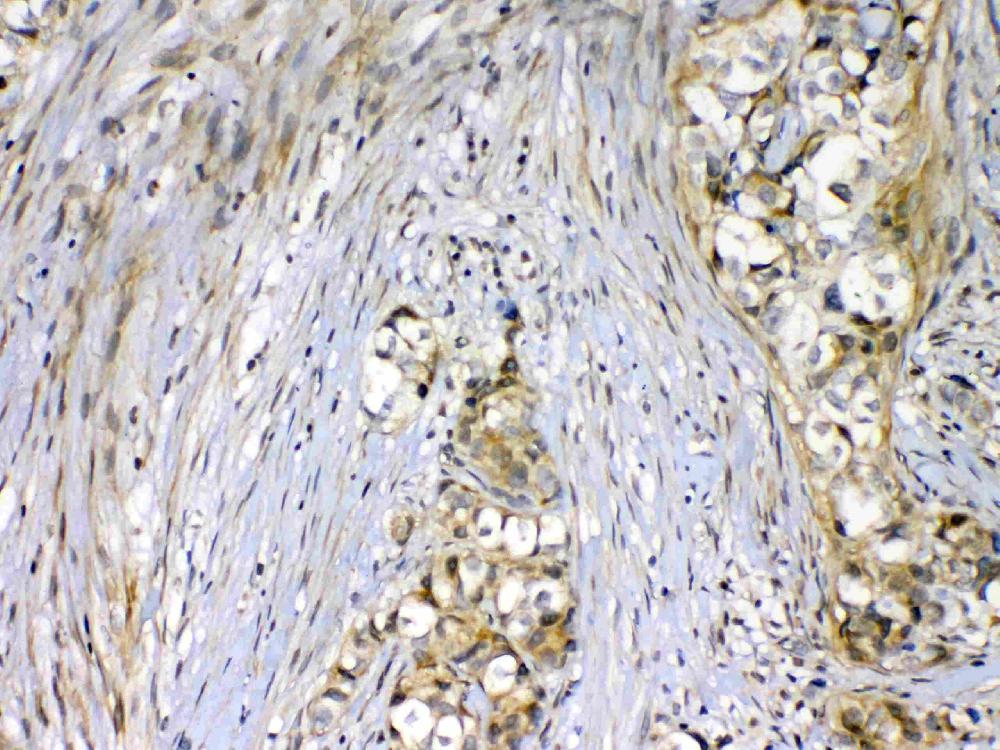

IHC analysis of VEGFR2/KDR using anti-VEGFR2/KDR antibody (A00901-2).

VEGFR2/KDR was detected in a paraffin-embedded section of human mammary cancer tissue. Biotinylated goat anti-rabbit IgG was used as secondary antibody. The tissue section was incubated with rabbit anti-VEGFR2/KDR Antibody (A00901-2) at a dilution of 1:200 and developed using Strepavidin-Biotin-Complex (SABC) (Catalog # SA1022) with DAB (Catalog # AR1027) as the chromogen.